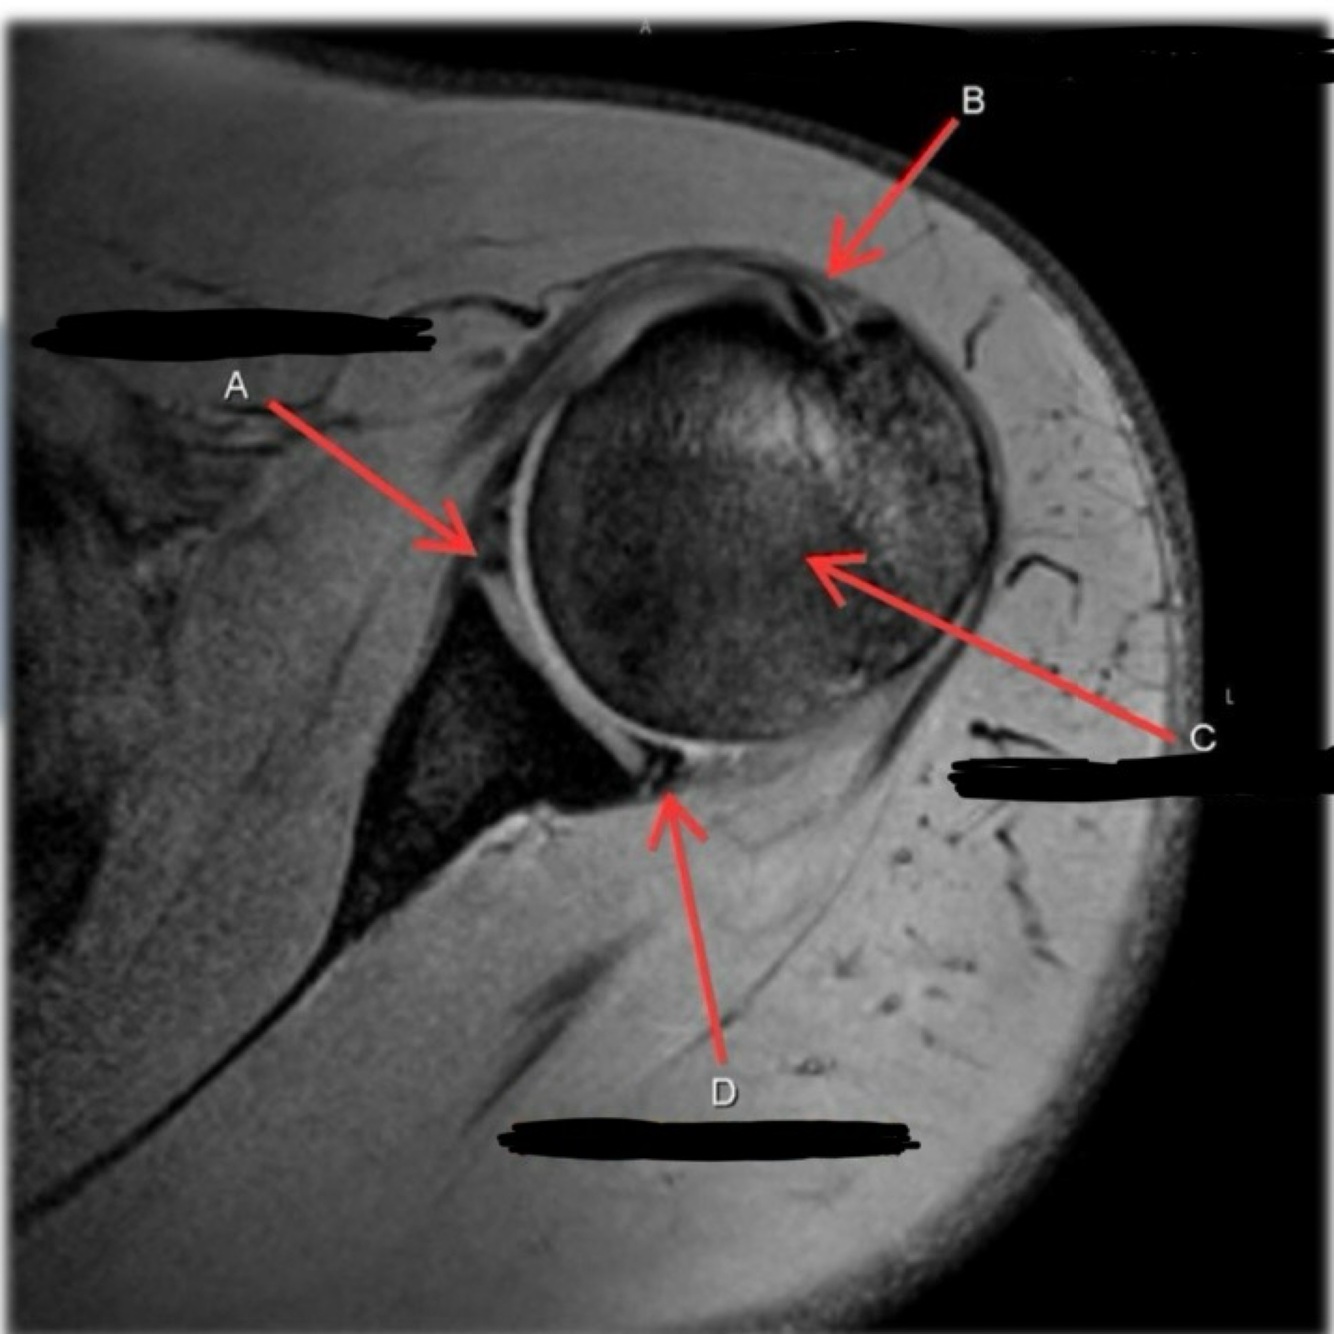

3

4

5

Perfectly

11

Q

What is letter A?

A

ANTERIOR LABRUM

How well did you know this?

1

Not at all

2

12

What is letter B?

BICEPS TENDON (LONG HEAD)

13

What is letter C?

HEAD OF HUMERUS

14

What is letter D?

POSTERIOR LABRUM